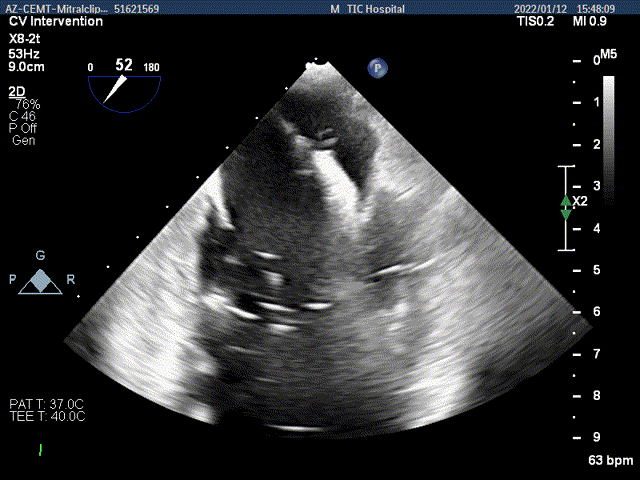

术前超声评估

术前超声诊断

Bicom:MR(重度),返流束宽12mm,返流面积10.3cm2,PISA法定量EROA:

0.77cm2,Rvol:115ml,RF:35%,r:12mm。

二尖瓣返流频谱呈全收缩期

肺静脉血流频谱呈收缩期反向

3D MV View:二尖瓣AC区为主(累及部分1区)脱垂并腱索断裂

3D-color MV view:大量返流,主要来源于AC区

Qlab软件勾画估测瓣口面积约:6.89cm2

二尖瓣口平均跨瓣压差:3mmHg

TEE Bicom view:二尖瓣AC区为主(累及部分1区)脱垂并腱索断裂。

Color-view:大量返流,主要来源于AC区